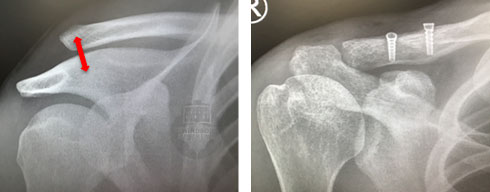

X-ray of acute high grade AC joint dislocation

A pre-op and post-op image of a grade 5 AC separation reconstructed with LARS ligament.